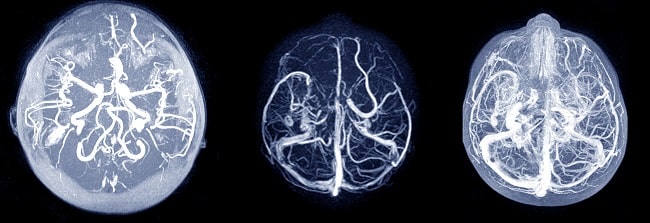

Unruptured intracranial aneurysm (UIA) merupakan pelebaran pembuluh darah arteri otak yang bersifat rentan mengalami ruptur. Rupturnya aneurisma intrakranial akan menyebabkan perdarahan intrakranial atau subarachnoid haemorrhage (SAH) , yang merupakan jenis stroke dengan prognosis yang buruk.[1-3]

Secara klinis, UIA dapat menimbulkan gejala pertumbuhan aneurisma atau sebaliknya tidak menunjukkan gejala dalam kurun waktu yang lama. Aneurisma asimptomatik umumnya ditemukan secara tidak sengaja saat pasien pemeriksaan radiologi kepala akibat kondisi medis lain, misalnya cedera otak traumatik.[1-3]